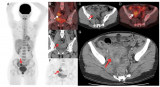

靶向MC1R的Ac-225治疗性核药完成首例患者给药,Alpha-9 Oncology的黑色素瘤诊疗一体化项目取得重要进展

2025年12月4日,临床阶段的放射性药物研发公司Alpha-9 Oncology宣布,已启动一项I期研究,并完成首例患者给药。该研究旨在评估A9-3408的安全性、剂量学及剂量递增情况,这是一种新型靶向黑色素皮质素1受体(MC1R)的Ac-225核素药物,用于治疗经标准疗法治疗后病情进展的MC1R阳性黑色素瘤患者。这一里程碑式的进展推动了Alpha-9的黑色素瘤项目。该项目于去年随着A9-3202的启动而首次进入临床阶段,A9-3202是一种基于Ga-68的显像剂,用于评估MC1R的表... 2025-12-06 核医药放射性药物